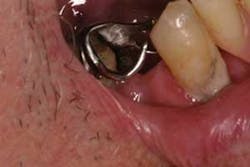

Pathogenesis: Normally, the clinical sign of a factitial injury is one in which the patient has produced an ulceration, hard tissue damage, or trauma to any tissue. In this case, the appliance is to blame. Mr. Saunders was aware of the missing teeth and the unstable position of the appliance, but he continued to wear the appliance. He was not aware that the appliance could become imbedded in tissue, but as time has progressed, the end of the metal appliance clasp has continued to become worn and even somewhat pointed (Figures 2 and 3).

Dental implications: The appliance for Mr. Saunders obviously no longer fits his dentition since he has lost the teeth anchoring the appliance in place. This could be a dangerous situation for Mr. Saunders since he has already suffered an injury while driving an automobile. The appliance is moveable and does not remain safely in place. The appliance became dislodged while the patient was driving, and he may have quickly reacted, and forced the appliance clasp deep into the tissue. As the bleeding became evident, he became even more distraught and probably put additional pressure on the appliance.